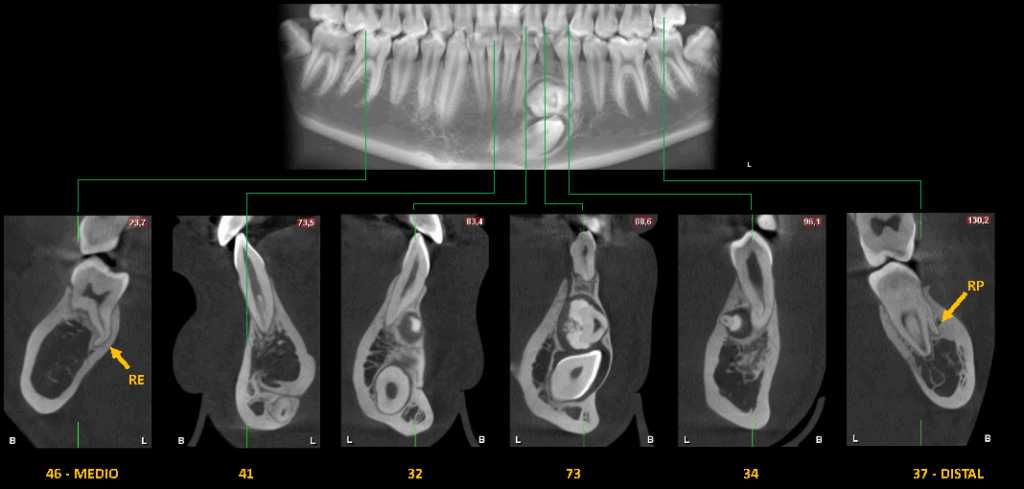

Asimismo, en el maxilar inferior se observa una imagen hiperdensa (OD) de densidad dentaria delimitada por un halo isodenso, ubicada entre las raíces de las piezas 34 y 32, que se extiende hacia las regiones linguales de las piezas 35 y 42.

Esta lesión ocasiona la impactación de la pieza 33 y genera expansión de la cortical ósea vestibular.

Finalmente, se identifica la presencia de una raíz adicional vestibular (RP) en la raíz mesial de la pieza 37; y una raíz adicional lingual (RE) en la pieza 46, la cual presenta una dilaceración radicular.

CORTES TRANSAXIALES